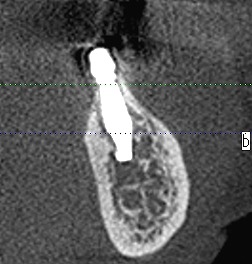

左下の6番部になります

6番部になります

インプラントの埋入位置も制限され神経までの距離も近くなります